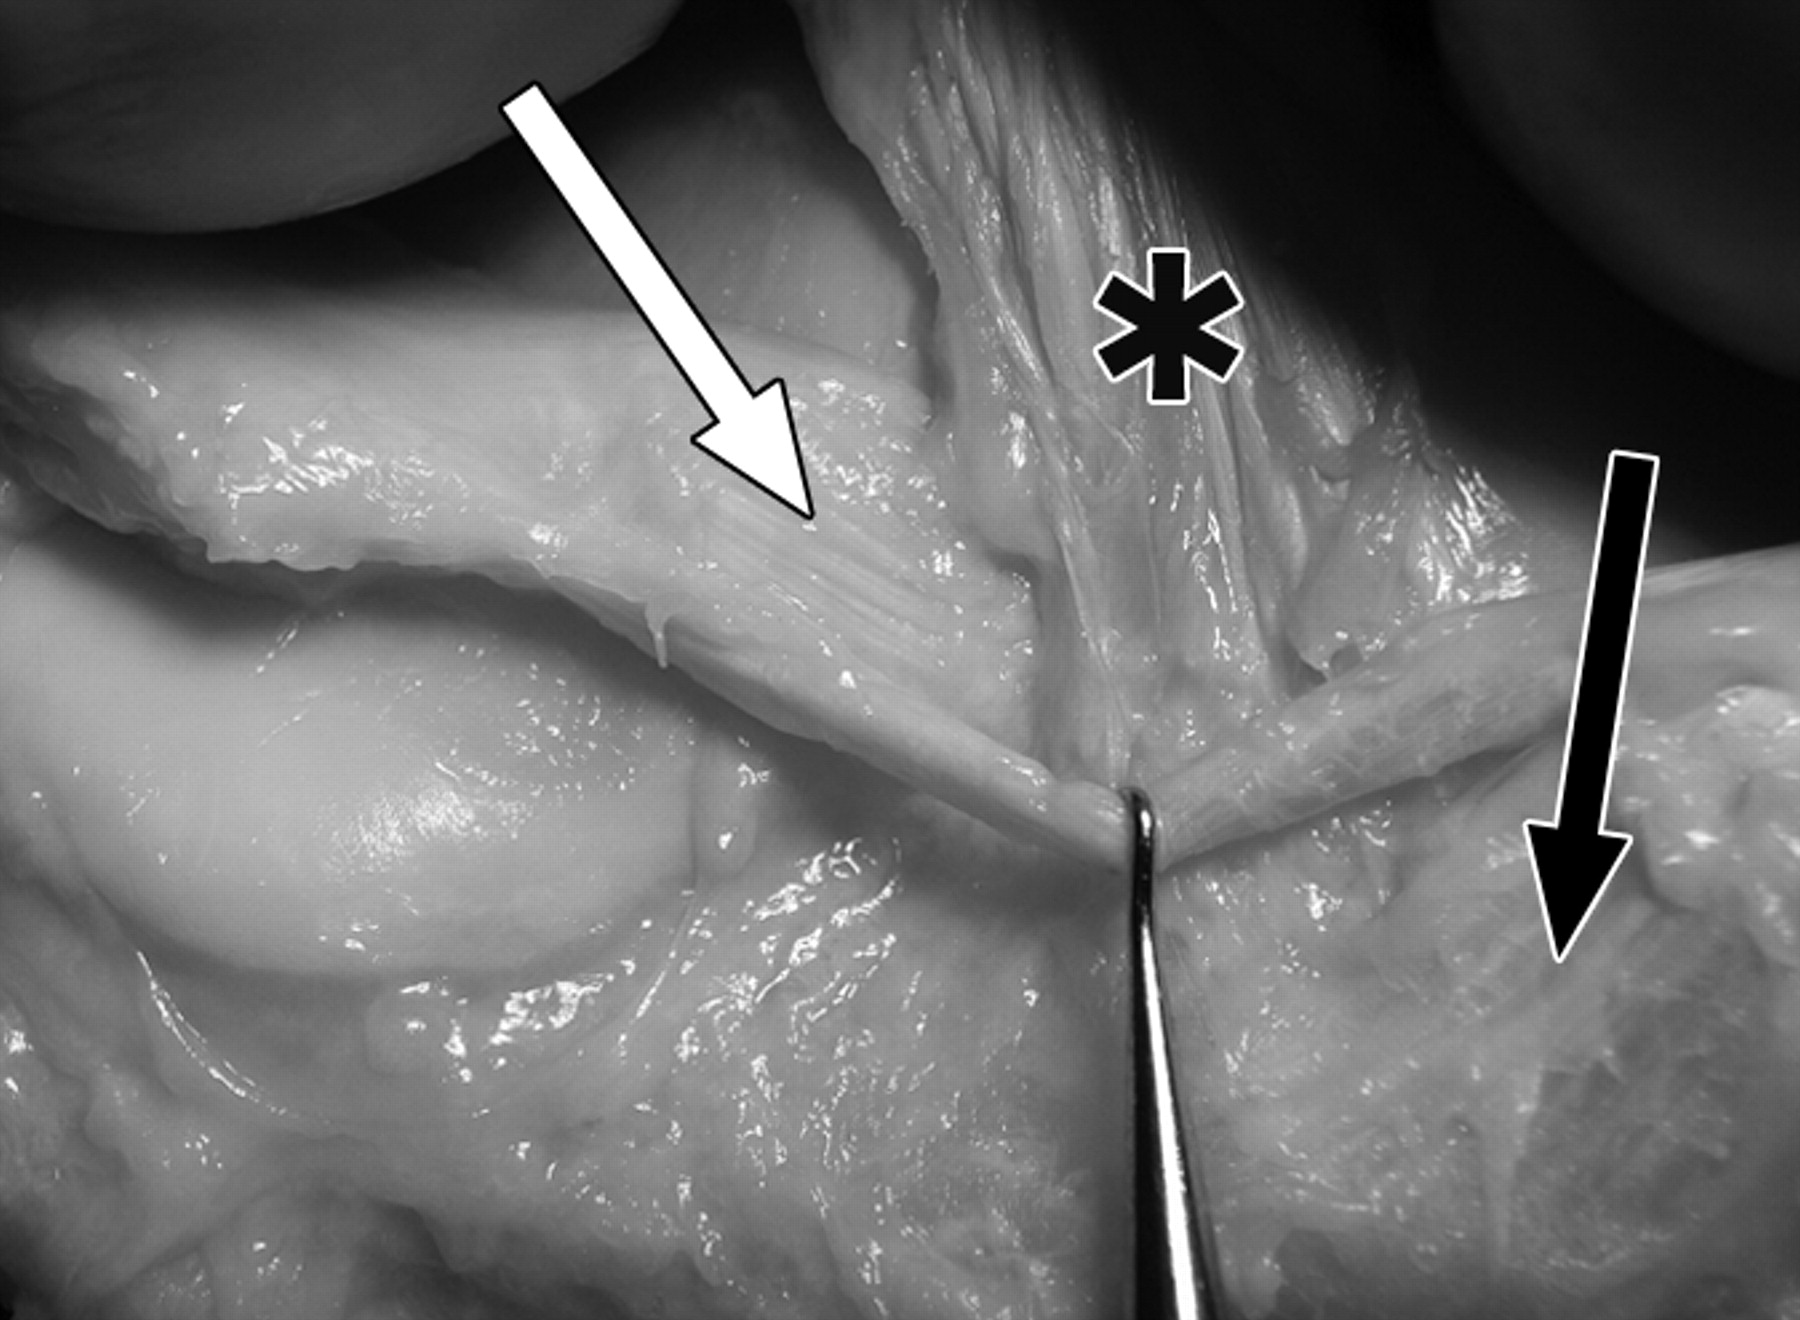

图1B-59岁男性大体标本。

黑色长箭头表示内侧半月板(MM)前根;黑色短箭头表示内侧半月板后根;白色长箭头表示外侧半月板(LM)前根;白色短箭头表示外侧半月板后根。主视图显示了与前交叉韧带(星号)、后交叉韧带(P)、后股关节Wrisberg韧带(黑色箭头)和膝横韧带(白色箭头)的关系。